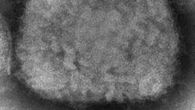

La viruela del mono, o ortopoxvirus símico, fue identificada en humanos en 1970 y es considerada menos peligrosa que la viruela, de la misma familia, erradicada en 1980.

Se trata de una enfermedad rara, provocada por un virus transmitido por animales infectados.